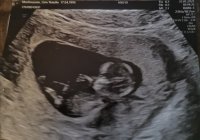

15 uker + 1 eller 2 dager, 120 g, 10 cm

Aktiv liten frisk baby som sprellet og snudde seg rett som det var! Hun var usikker, men mest sannsynlig er det en liten gutt. En måned til OUL og (kanskje) en endelig bekreftelse på det bildet ble sidelengs her, men SE! Det er jo et lite miniatyrmenneske inni der!